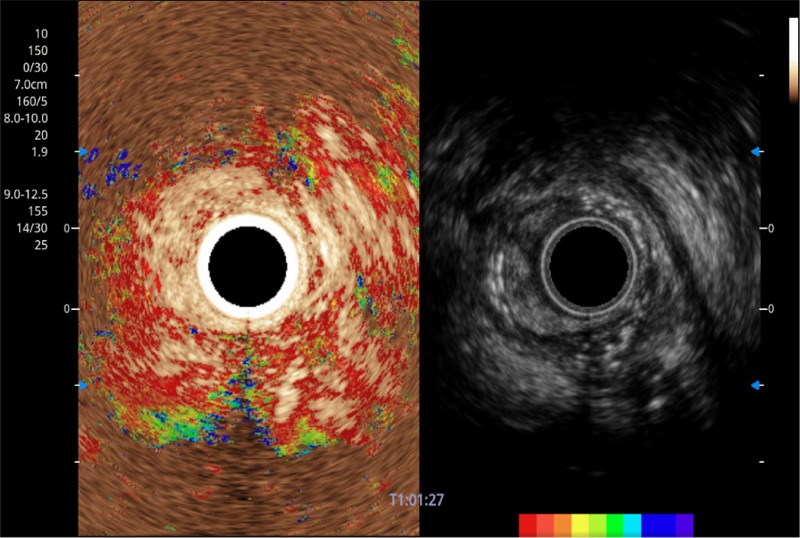

• 非线性融合造影

融合谐波技术

动态声压控制技术

TIC时间强度分析曲线

具有四种造影成像效果